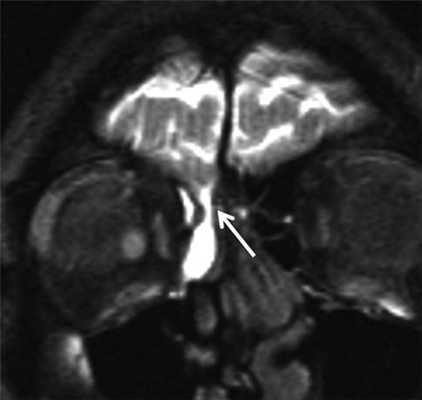

МРТ-цистернография. Аксиальная Т2-взвешенная МРТ головного мозга, цветовая обработка изображения. Ликворрея через наружный слуховой проход слева.

Ликворрея - утечка ликвора может быть из носа (риноррея) и из наружного слухового прохода (оторрея). При этом должно быть травматическое или операционное повреждение черепа. Ликыор вытекает через фистулу из субдурального или субарахноидального пространства. При подозрении на ликворрею капли вытекающей жидкости сперва идентифицируют как СМЖ. Следующим этапом выполняют КТ тонкими срезами с захватом лицевого черепа, пазух и височных костей. Следующим этапом выполняют КТ-цистернографию или МРТ головного мозга, иногда с МР-цистернографией. При МРТ головного мозга обычно удается увидеть постравматическую грыжу через решетчатую кость или височную кость, соответственно. При МРТ головного мозга могут также определяться гипотензивные синдромы после люмбальной пункции или спонтанные. Гипотензивный синдром при МРТ головного мозга выглядит как пахименингит - утолщение и контрастирование оболочек часто в сочетании с субдуральной гигромой или гематомой. Желудочки при МРТ выглядят суженными, гипофиз, напротив, увеличенным. Венозный отток по яремным венам снижен, что приводит к расширению синусрв при МР-венографии.

МРТ головного мозга. Т2-взвешенная корональная МРТ. Стрелкой показана фистула.